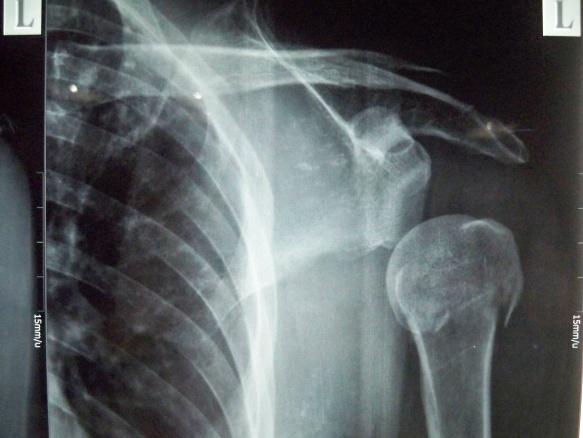

左肱骨外科颈骨折伴左肩关节脱位

患者男,43岁,从约3米高处坠落,左肩关节及上臂肿胀、疼痛活动受限3天入院。

查体:一般状况好,神志清楚,自动**。体温37.1℃,脉搏、呼吸、血压正常。头颅五官胸腹未见异常。脊柱无畸形及压痛。左肩关节明显肿胀,无皮肤裂口,可见大量皮肤瘀斑。左肩关节活动受限。左上肢皮肤浅感觉正常。左手各指感觉正常,左肩处叩击疼。